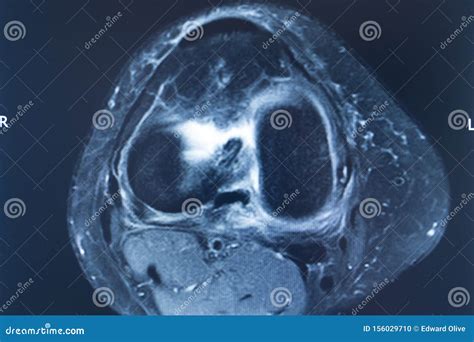

An Mcl Tear Mri is a non-invasive imaging technique that provides detailed images of the knee joint. MRI uses magnetic fields and radio waves to create cross-sectional images of the body’s internal structures. This allows healthcare professionals to visualize the MCL and other soft tissues in the knee, identifying any tears or damage.

During an *Mcl Tear Mri*, the patient lies on a table that slides into a large, cylindrical machine. The procedure is painless and typically takes about 30-60 minutes. The MRI machine captures multiple images from different angles, providing a comprehensive view of the knee joint.

An *Mcl Tear Mri* is particularly useful for differentiating between an MCL tear and other knee injuries, such as meniscal tears or anterior cruciate ligament (ACL) injuries. This information is crucial for developing an appropriate treatment plan.